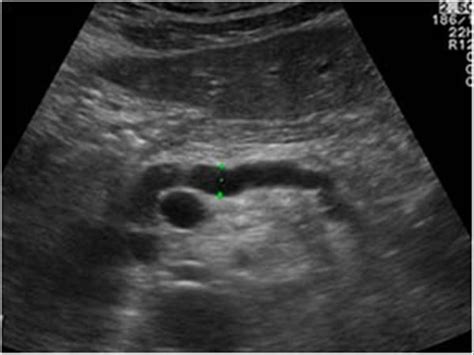

A patient presents with a sudden onset of moderate to severe abdominal pain radiating to the back, nausea, and vomiting. Laboratory tests show elevated amylase and lipase. Ultrasound demonstrates an enlarged hypoechoic pancreas with irregular borders and peripancreatic fluid collections. What is the most likely diagnosis?

Acute pancreatitis